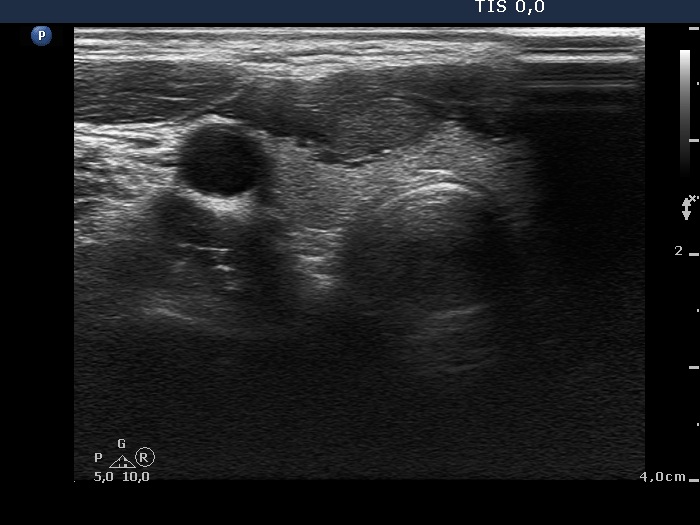

Transverse scan |

The nodule is brighter than the strap muscle while darker than the extranodular tissue and does not show any suspicious sign. This is an EU-TIRADS 4 lesion.